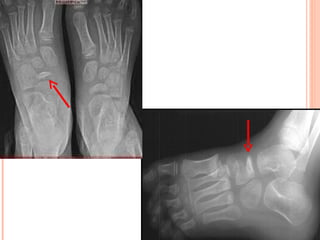

Enfermedad de Freiberg o Kohler II

 Destrucción   de   cabeza   de   2do

Mecanismo de acción

 Mujeres jóvenes por microtraumatismos

por uso de tacos altos

Cuadro Clínico

 Doloren dorso del pie que aumenta

durante la marcha o a la palpación.

 Engrosamiento  irregular similar a un

verdadero rodete óseo.

Cuadro Radiológico

   Rx sucesivas = destrucción gradual de la epífisis

metatarsal.

   Carilla   articular    deformada,     irregular,

ensanchada, agrietada y finalmente aplanada.

   Cabeza metatarsiana ensanchada en sentido

transversal y disminuida de altura.

   Espacio articular aparece muy aumentado.